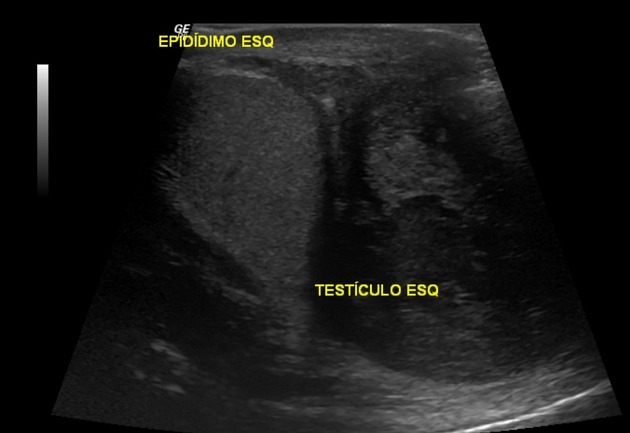

Q

Paratesticular mass in young adolescent

A

Paratesticular rhabdomyosarcoma